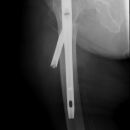

pertrochantäre Femurfraktur